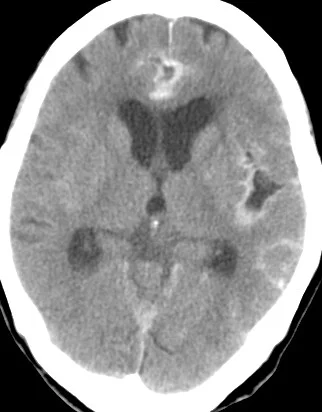

這題的重點是判斷蜘蛛網膜下腔出血(SAH)的影像特徵,並了解其後續的診斷與處理。圖片中可以看到腦部電腦斷層掃描顯示腦溝和腦池內有明顯的白色高密度影像,這就是急性出血的表現。